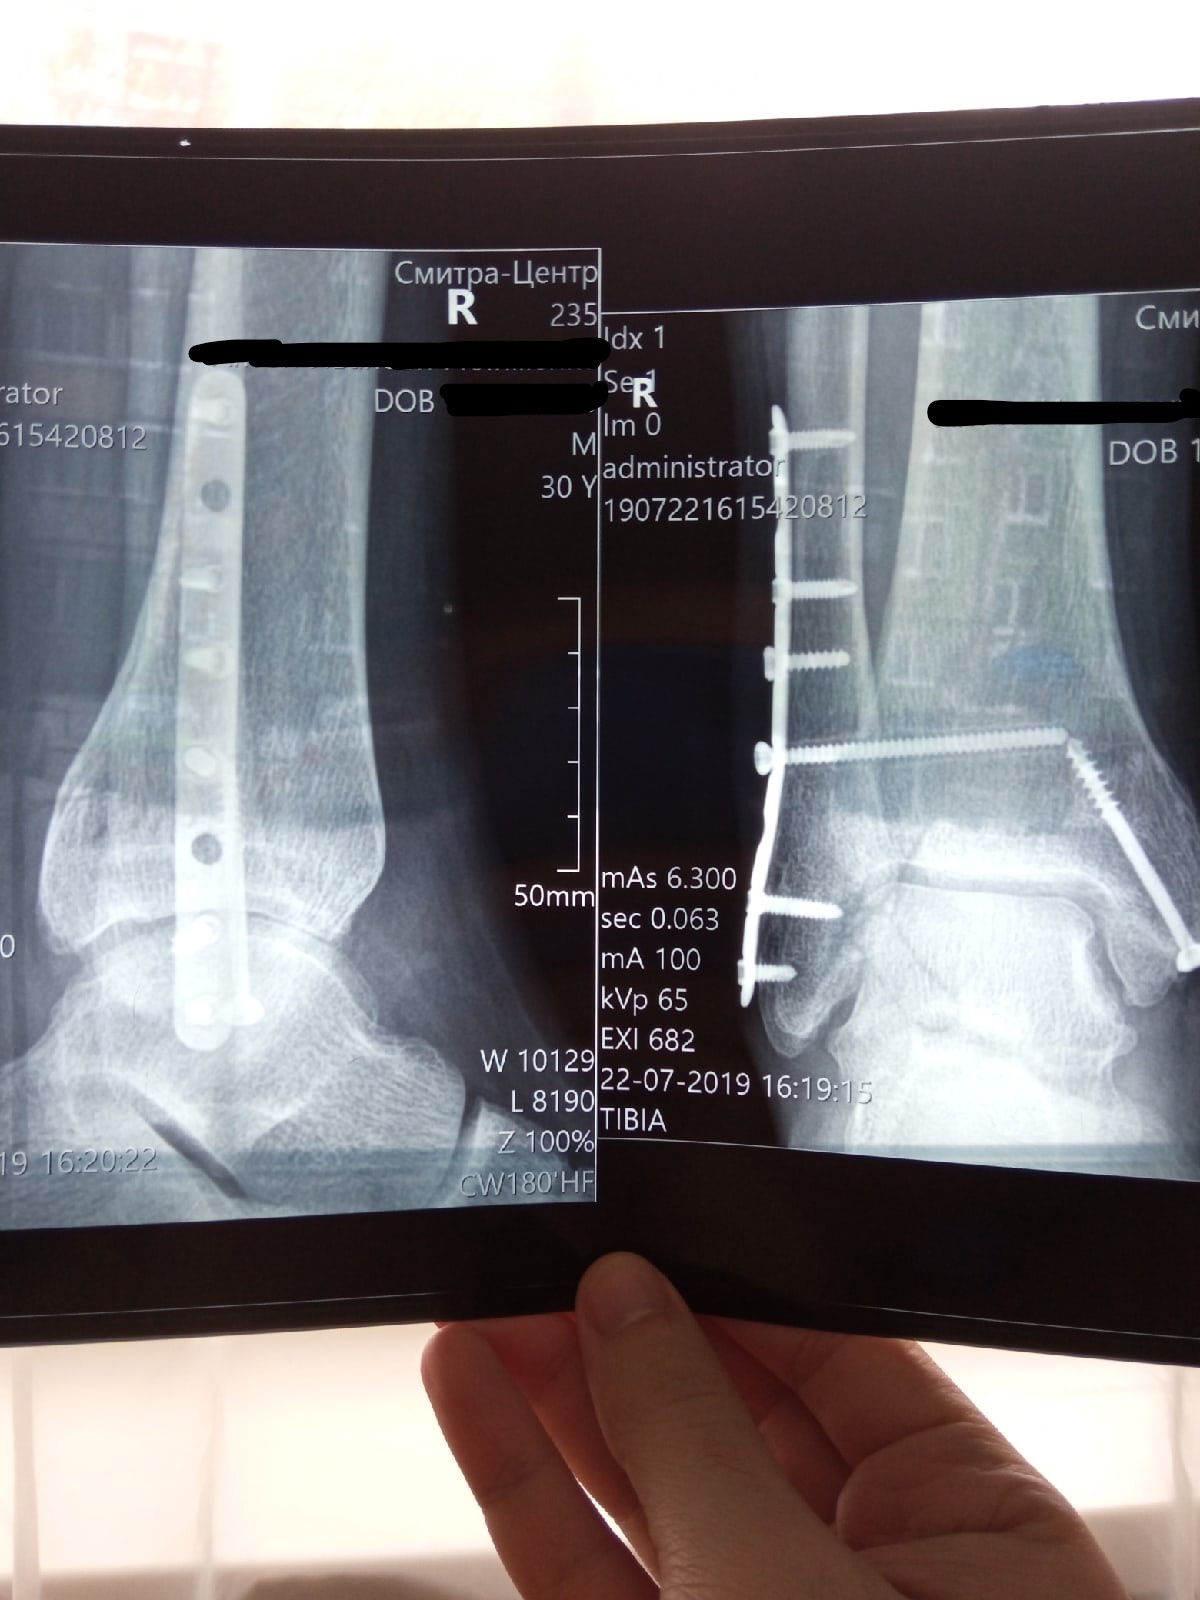

2 недели назад зашили сухожилие на бедре и мышцу, операция не сказать, что ахти как тяжело, но наступать на ногу нельзя от слова Вообще в течение 6 недель и потом с костыликами потихоньку...

Оказалось- у нас перед входной дверью ступенька, которую никто не замечал ( все удивленно: У вас ступенька?) Опираясь на костыли, запрыгиваю на здоровой ноге, на которой 20 лет назад тоже была порвана связка, (последствия веселой молодости).